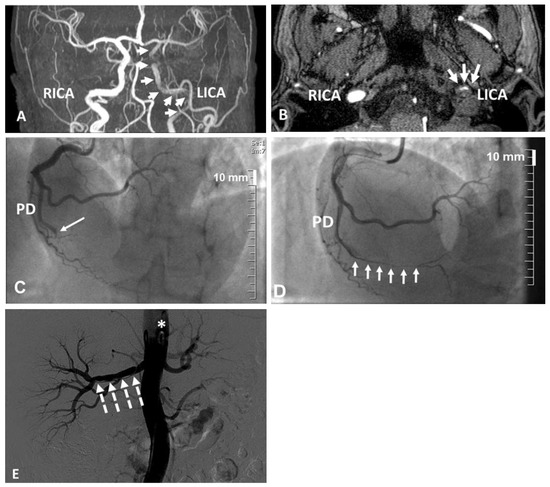

We present a case of false deployment of a self-expandable transcatheter aortic valve implantation (TAVI) prosthesis due to inadvertent and incorrect release of an eyelet in the crown of the valve resulting in a tilted valve. Hence the prosthesis had...